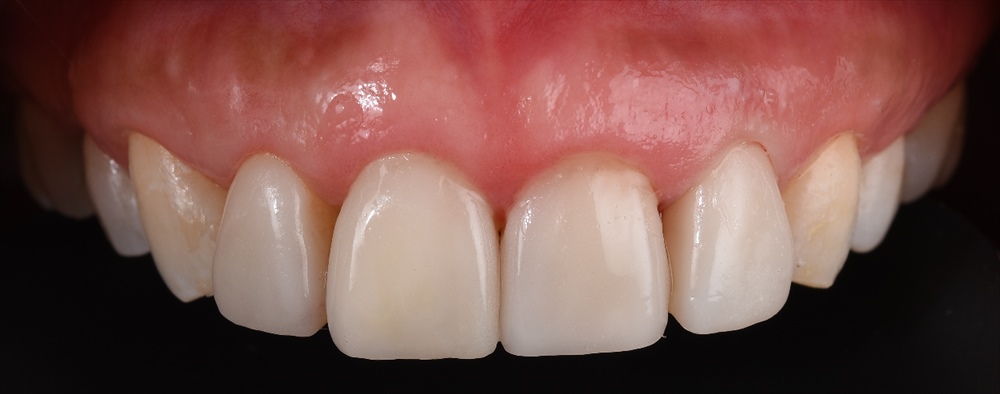

先日 術後

ラミネートべニアをセットしました。

術前

笑っても歯肉が見えにくいので更にお綺麗になりました。

患者さまも喜んで頂き嬉しかったです!